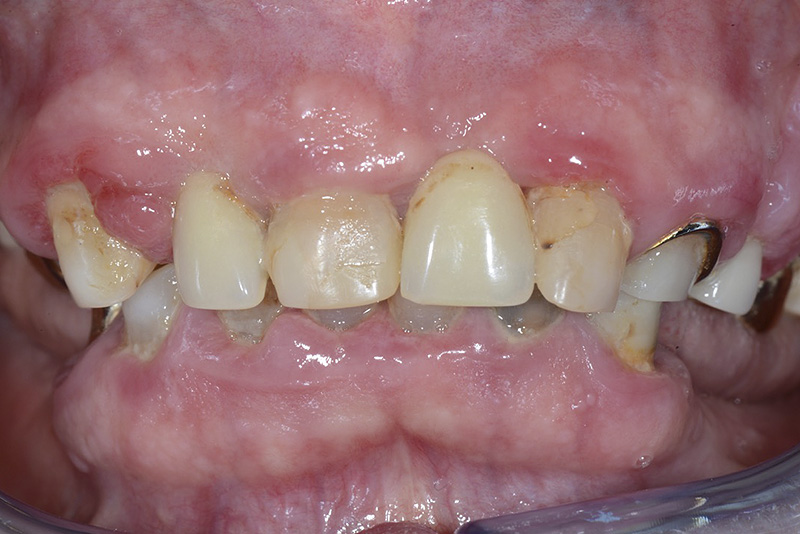

PREMESSA: in seguito all’estrazione dell’incisivo laterale superiore di destra, resasi necessaria per cause batteriche, si decide di affrontare il caso con il posizionamento di un impianto in sostituzione dell’elemento mancante dopo guarigione del sito infetto. Con tecniche rigenerative sia dei tessuti ossei mancanti a causa dell’infezione pregressa, sia dei tessuti gengivali che appaiono inizialmente troppo spostati in alto, si ripristina una corretta morfologia delle parabole (contorni) gengivali e delle papille interdentali (triangoli di gengiva tra due denti vicini).

Vengono utilizzati 2 tipi di provvisori: il primo, cementato ai denti vicini, viene utilizzato dal momento dell’estrazione del dente fino ad impianto osteointegrato (circa 6 mesi); il secondo, avvitato direttamente all’impianto, ha una funzione di prova estetica ma soprattutto di guida per la maturazione dei tessuti gengivali peri-implantari portandoli verso la maturazione completa prima di posizionare la corona finale in disilicato di litio.